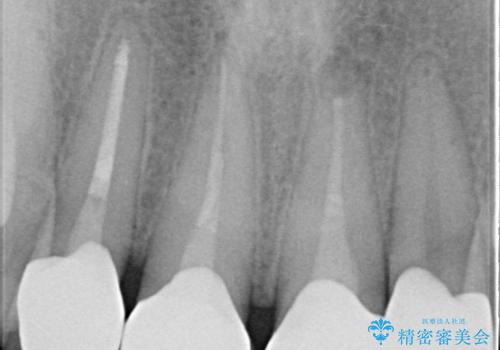

- 前歯のかぶせ物を自然な色味のものにしたいとのことで、来院されました。

保険適用のかぶせ物が装着されており、適合も悪く、変色している状態でした。

土台からの、再治療を行い、オールセラミッククラウンの装着を行う計画としました。

審美的な改善はもちろんのこと、ぴったりとしたものを装着することで、歯茎の発赤も改善されました。